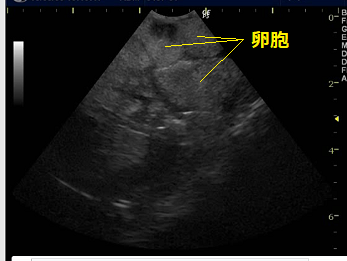

卵胞鬱滞を呈している爬虫類(ミシシッピアカミミガメの一症例およびサバンナモニターの一症例)に対して、酢酸リュープロレリン(商品名:リュープリン)を用いて治療を行う機会を得たため、2017年のエキゾチックペット研究会にて症例発表を行った。

爬虫類における生殖器疾患は比較的多く、中でも卵塞性が問題になりやすい。卵胞鬱滞は発生機序が明確になってはおらず、外科的な卵巣・卵管摘出術が主な治療法であり、内科的な治療法はいまだ確立されていない。

爬虫類における生殖器疾患は比較的多く、中でも卵塞性が問題になりやすい。卵胞鬱滞は発生機序が明確になってはおらず、外科的な卵巣・卵管摘出術が主な治療法であり、内科的な治療法はいまだ確立されていない。